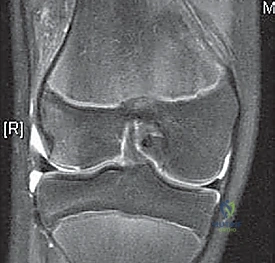

- MRI Scan: Highly recommended for all patients with a large traumatic effusion due to the high rate of occult articular or osteoarticular injury.

* Osteochondral Lesions: Crucial for determining size, location, and potential for repair versus removal.

* Bone Bruise Pattern: Confirms patellar dislocation (medial patella and lateral femoral condyle).

* Anatomical Risk Factors: Assesses patella alta, trochlear dysplasia, tibial tubercle-trochlear groove (TT-TG) distance.

* Bone Bruises: MRI often reveals increased signal on the medial patella and the midportion of the lateral femoral condyle. This distinct pattern helps differentiate it from ACL tears.